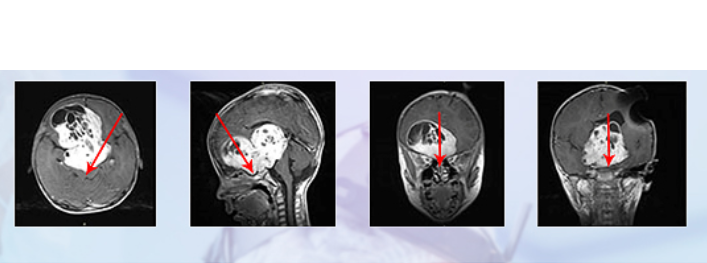

德國(guó)巴教授INI手術(shù)結(jié)果:

è§??¥????è??è′¨??¤??????

更新診斷“視神經(jīng)膠質(zhì)瘤”,

腫瘤全切,未殘留長(zhǎng)期神經(jīng)功能障礙,

術(shù)后兩周出院,視力明顯好轉(zhuǎn),

可自行站立、短距離行走。

手術(shù)過(guò)程記錄:通過(guò)額骨顱骨開顱術(shù)和大腦半球間穹窿入路腫瘤切除術(shù)直至Monro孔(室間孔),并沿著腦室壁向中腦行進(jìn)。右側(cè)視神經(jīng)被腫瘤浸潤(rùn)包裹,但是左側(cè)視神經(jīng)被小心地從腫瘤腫塊中剝離出來(lái),垂體腺和垂體柄也被小心的保護(hù)起來(lái)。沒(méi)有術(shù)中并發(fā)癥。

術(shù)后病理結(jié)果:小冬患的是毛細(xì)胞型星形細(xì)胞瘤,WHO I級(jí),是一種低級(jí)別膠質(zhì)瘤。根據(jù)美國(guó)腦膠質(zhì)瘤NCCN治療指南及臨床數(shù)據(jù)統(tǒng)計(jì)提示,術(shù)后不需要進(jìn)行放化療等治療(放化療對(duì)病情控制無(wú)益,但是對(duì)身體的傷害大于獲益),而且20年總體生存率87%±0.8%。

術(shù)后1年,小冬一家來(lái)到INC面對(duì)面咨詢“巴教授”,原本已經(jīng)失明的小冬現(xiàn)在視力漸漸恢復(fù)了,復(fù)查后MRI影像也顯示腫瘤并無(wú)增長(zhǎng),小朋友恢復(fù)了以往的活潑可愛(ài)。